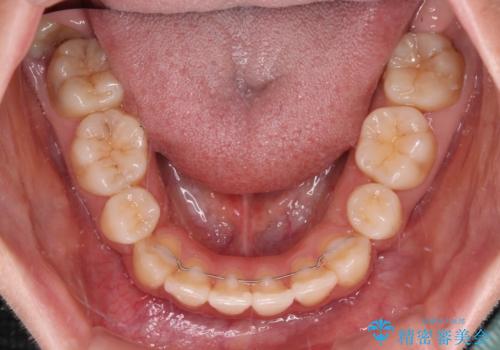

- メタルブラケット

- 1年5ヶ月

上下ともに歯列が前方に突出していたため、上下左右の第一小臼歯4本を抜去し、ワイヤー装置による矯正治療を行うこととしました。

上下左右4本抜歯する場合には、通常2年から2年半ほどの期間を要しますが、僅か1年半で終了することができました。

- 矯正治療後の保定が不十分だと後戻り(元の位置に戻ろうとする動き)をします